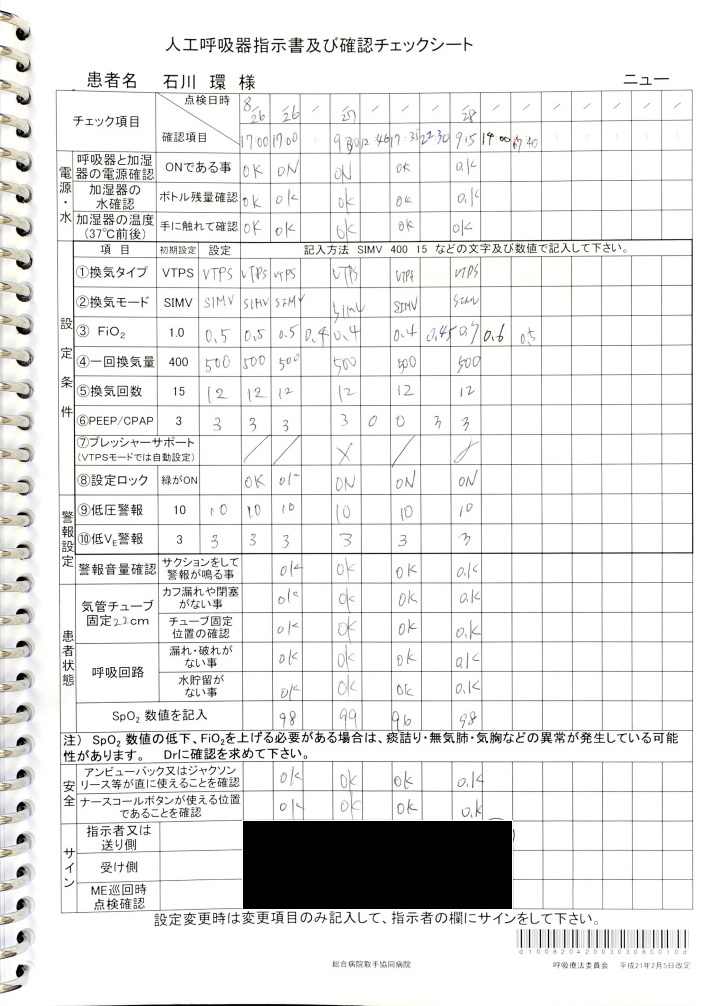

- 8月28日0時過ぎ:「心タンポナーデ」、「心嚢穿刺」の記載

心エコーにて心嚢水増量を認め、血圧50mmHgまで低下したため心嚢穿刺施行、との記載あり。

証拠:カルテ記載・病状説明用紙

- 8月25~28日:ショックに伴う乏尿・無尿・危篤状態

8月25日:尿量779ml/日、8月26日21:30~8月27日5:30:尿量28 ml, 8月27日5:30~13:30:尿量15 ml, 13:30~21:30:尿量4 ml, 21:30~8月28日5:30:尿量144 ml(ショックに伴い無尿、ショック解除に伴い尿量増加。)

証拠:CCU看護記録(尿量)

ショック肝(重症肝不全:ピーク値:AST 4018 U/l, ALT 3177 U/l)、ショック腎(重症腎不全:Cre 5.15 mg/dl)の進行。ショック解除後、悪化なし。

証拠:血液検査データ

8月28日夜半過ぎにショック解除が行われたが、私たち家族への連絡もなく同意も取得していなかった。 私たち家族への着信記録もなかった。 私が心配になり病院に行くと、8月28日午前9時30分の時点で血圧110/60 mmHg, 心拍数100/minとショックから離脱していた。 医師は「夜間、さらに血圧が下がったため、エコーを当ててみると、心嚢水が貯留して心タンポナーデになっていたため、心嚢穿刺を行った」と私に事後報告した。「その原因はoozing型心破裂と言って、心筋梗塞で壊死して脆くなった心筋の隙間から心嚢内に血液が少しずつ漏れ出している状態であり、いずれにしても危険な状態」とのことであった。

このショック解除について、医師は「心嚢穿刺」と説明しカルテにも「心嚢穿刺術」と記載されているが、生命保険診断書には「心嚢穿刺術」の記載がなく、レセプトには「心嚢水」ではなく「胸水」と記載されており、記録間に矛盾がある。心嚢への出血のみで輸血が必要になるほどの貧血になることは考えられず、それよりも大きなスペース(胸腔)への出血が必ず起こっていたと考えられる。実際、「胸水穿刺」と考えると、輸血が必要だったこと、出血性ショックも起こっていた可能性が高いことなどを含め、前後の経過が矛盾なく説明できることから、実際に起こっていた病態は胸腔内への出血に伴う緊張性血胸、出血性ショックで、ショック解除のために行われた手技は胸水穿刺だった可能性が高いと考えられる。

入院した8月25日から8月28日にかけて血液検査で肝機能の値(AST, ALT)、腎機能の値(Cre)が急激に上昇し、肝機能の値のピーク値は8月28日のAST 4018 U/l, ALT 3177 U/lと重度の肝不全であり、経過からはショック肝と考えられる。 また腎機能を示すCreは、8月26日にCre 0.82 mg/dl, 8月27日にCre 2.66 mg/dl, 8月28日にCre 5.15 mg/dlと腎不全が日単位で急激に進行しており、血圧低下の経過と一致しており、ショック腎と考えられる。